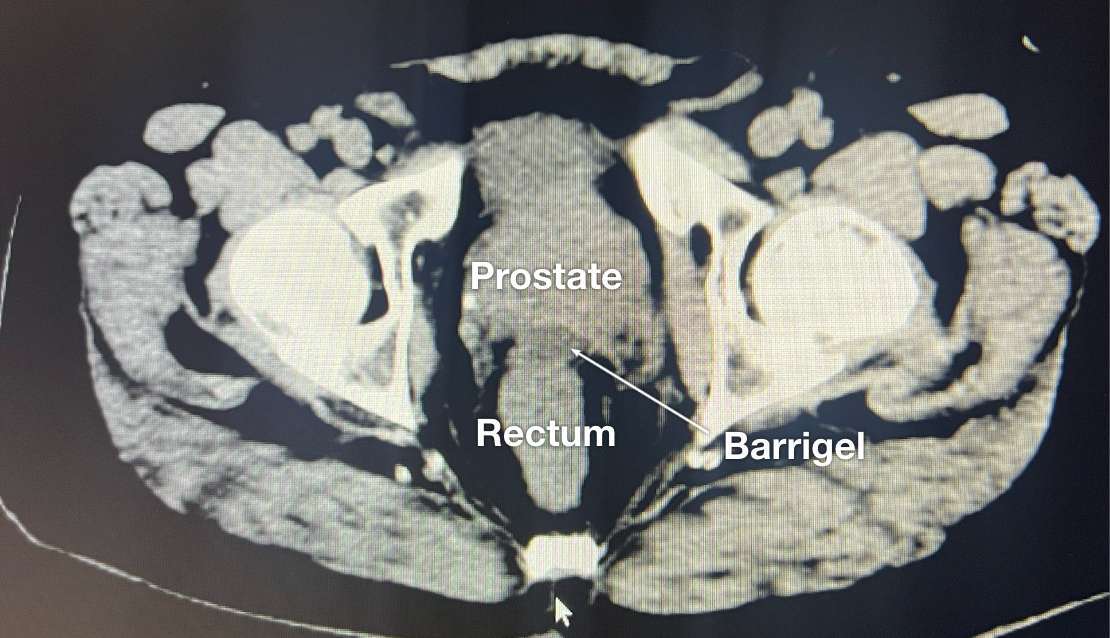

CT IMAGES

CT image courtesy of Glen Gejerman, MD

Radiation Oncologist; New Jersey, United States